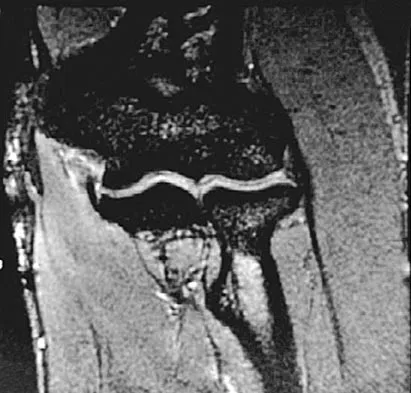

Which of the following primary prognostic factors best predicts the outcome of the knee lesion shown in Figure 22?